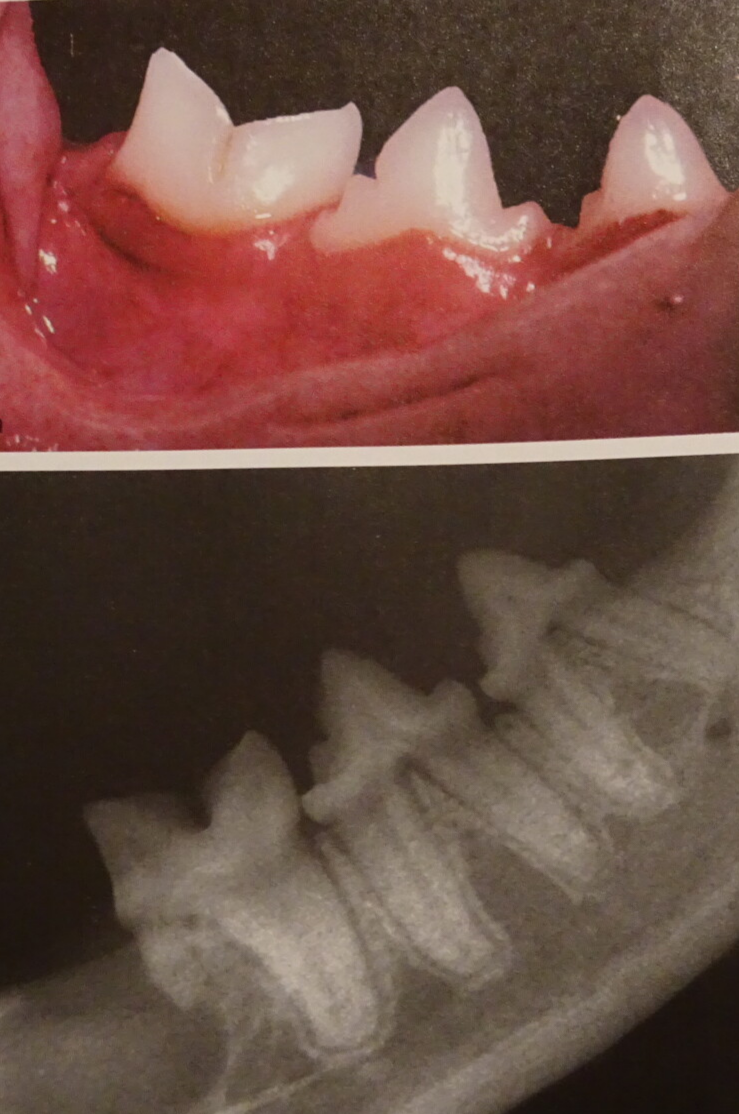

Voorbeelden van verdoken tand problemen . Op radiografie zie je wat zich onder het tandvlees afspeelt.

Voorbeelden van tandbehandeling: Opsporen , blootleggen tandwortel, doorzagen van de tanden en verwijdering van aangetaste tandwortel.